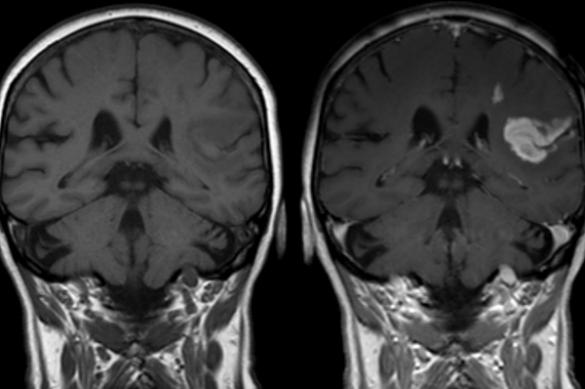

![]() | ![]() |

| Очаги демиелинизации на МРТ до и после лечения. Через 4 месяца от начала лечения видно уменьшение очагов – ремиелинизация (диагноз – рассеянный склероз, протекавший на фоне инфекции вирусом Эпштейн-Барр, микоплазмой и хламиией). Чем раньше начато лечение – тем лучше прогноз на восстановление. | |